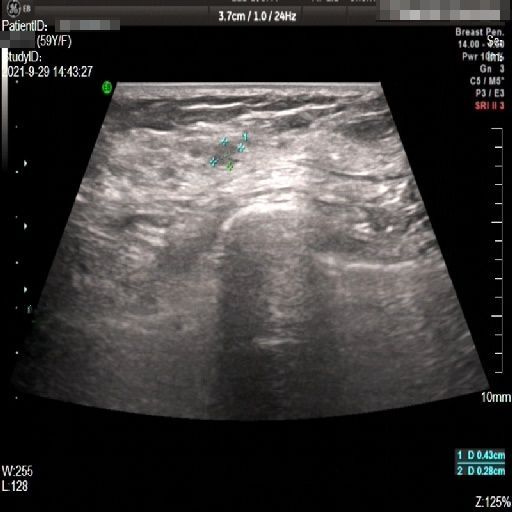

Images with certain annotations are considered noisy images in the context of the noise removal task, and corresponding images without these annotations are considered clean. Some typical images with various annotation are provided in Fig. 1.

(a)

(b)

(c)

Figure 1: Images with various annotations. (a) body marker annotation, (b) radical line annotation, (c) vascular flow annotation.